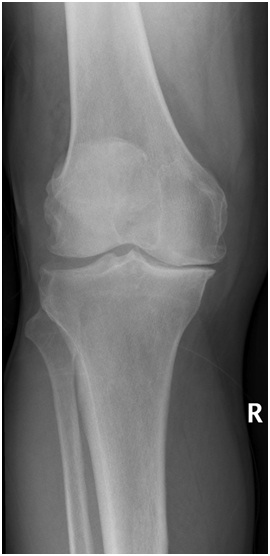

As we get older the cartilage in our joints becomes more brittle and is likely to wear out or degenerate. This can lead to osteoarthritis which is wearing out of the lining (articular) cartilage. In the early stages of arthritis pain is normally mild and only felt after exercise. It is usually a dull ache and may be associated with some swelling. As arthritis progresses the pain will become constant and more severe. It may be painful at rest and wake you up at night. The joint will often become stiff and may become deformed or angulated.

Many people develop arthritis with no known factors that have predisposed them. If you have had a significant injury to a joint it is more likely to develop arthritis. If you are severely overweight this puts stress on your joints and may lead to early arthritis. Other medical conditions can also lead to early arthritis. People who have childhood problems with their hips such as Congenital hip dysplasia, perthes disease and slipped Upper femoral Epiphyses are predisposed to developing hip osteo arthritis

In the early stages the pain can be treated with simple painkillers. It is important to keep the muscles in good shape and keep the joints moving. For this reason physiotherapy is often helpful. As the pain gets worse stronger and more frequent pain killers may be needed. Sometimes an injection of cortisone into the joint may be helpful. When the pain is severe and interfering with you life it may be appropriate to consider having a partial or full joint replacement.